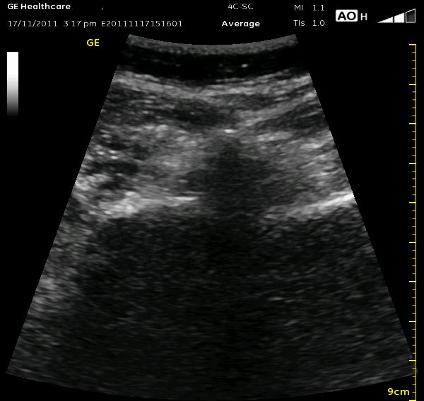

The ultrasound picture below is a midline transverse view between the Transverse Processes which will allow an out of plane or in plane (medial or lateral) needle approach. For any of these approach, it would be helpful to slide the probe laterally a few centimeters. Notice that the Lumbar Plexus estimation is in the posterior 1/3 of the Psoas Muscle belly. The Spinous Process does reach superficially because the beam is not crossing at its highest point. The Vertebral Body is likely larger than what is represented in the cartoon image, and the medial border of the Psoas Muscle is also estimated due to the bone shadow from the Lamina/Facet above.